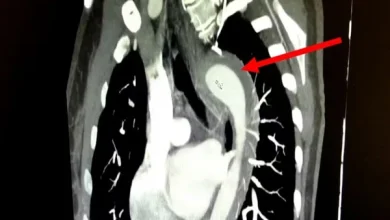

Mulher rompe aorta durante relação sexual e é levada às pressas para cirurgia

Uma mulher de 45 anos precisou passar por cirurgia de urgência após sofrer uma ruptura na aorta durante uma relação…